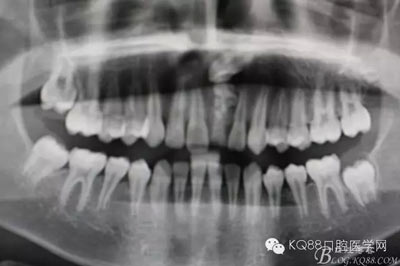

圖2.全景片影像檢查:牙冠接近鼻底,位置高,橫位阻生,正畸牽引有點(diǎn)困難,故同家長(zhǎng)溝通,有牽引失敗的可能。同時(shí)暫時(shí)保留乳Ⅰ。不影響孩子的美觀(guān)及發(fā)音。